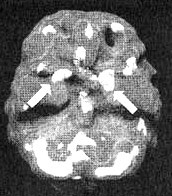

Мозг Билла — мозг влюбленного человека

Трехмерное изображение — активный мозг, вид снизу. Обратите внимание на повышенную активность базальных ганглиев слева и справа (помечено стрелками).

Повышенная активность базальных ганглиев задает нашему организму, даже в состоянии покоя, повышенные обороты и приводит к возникновению чувства тревоги, нервозности, напряжения и пессимизма. Почти у всех пациентов, проходивших у нас лечение по поводу панических состояний, которым проводилось сканирование мозга, отмечалась повышенная активность базальных ганглиев.